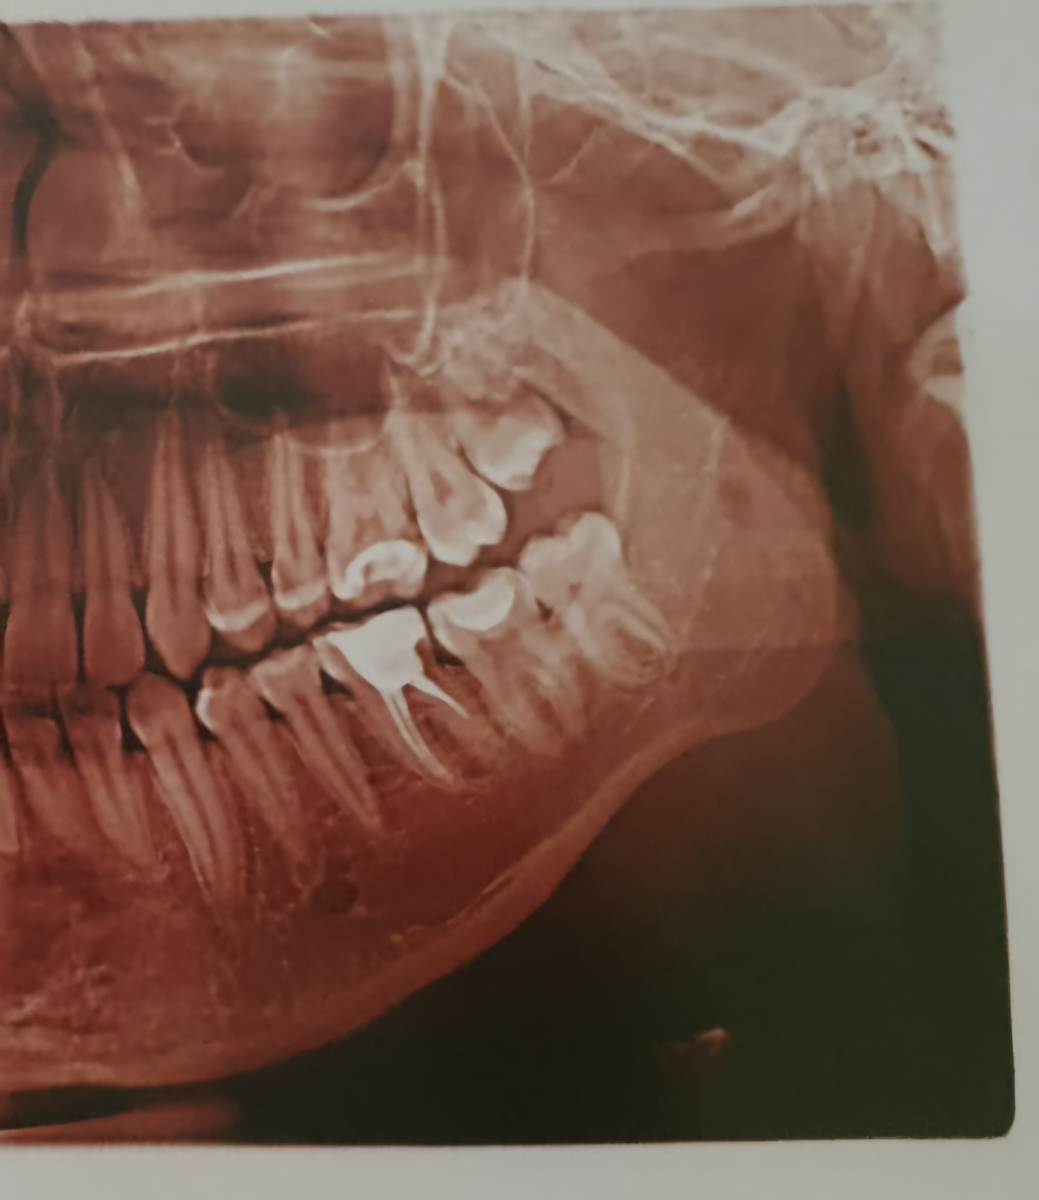

Л93 Опубликовано Понедельник в 19:05 Автор Поделиться Опубликовано Понедельник в 19:05 Этот снимок был сделан 6 лет назад перед началом лечения. Ссылка на комментарий

Женька Опубликовано Понедельник в 19:36 Поделиться Опубликовано Понедельник в 19:36 Здравствуйте! Криминала не вижу по Вашему 25 зубу. Но это лишь один срез, не дающий полной картины. По 8... интересно посмотреть в полости рта. Потому что на снимке 6 лет назад она действительно не прорезалась, а вот на свежем вполне себе должна жевать с нижней 8. Ссылка на комментарий

Л93 Опубликовано Вторник в 09:59 Автор Поделиться Опубликовано Вторник в 09:59 @red_butler вчерашний снимок кт в первом сообщении Ссылка на комментарий

wladdX Опубликовано Вторник в 21:40 Поделиться Опубликовано Вторник в 21:40 (изменено) Скорее всего виновен 25 Изменено Вторник в 21:41 пользователем wladdX Ссылка на комментарий

red_butler Опубликовано 16 часов назад Поделиться Опубликовано 16 часов назад Здравствуйте, требуется повторное лечение корневых каналов пятого зуба. почитайте эту тему Ссылка на комментарий